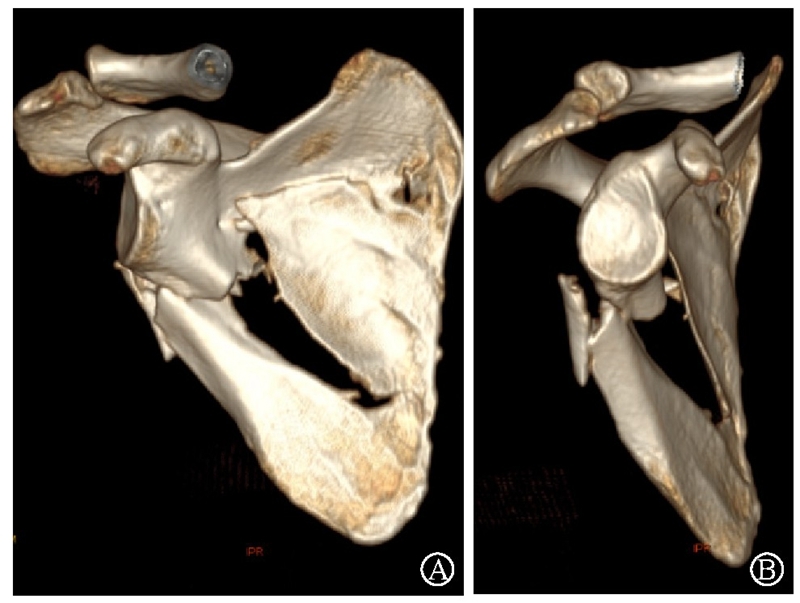

病例2为1例累及肩胛盂、肩胛颈和肩胛骨体部的复杂肩胛骨骨折(图11-12)。

图11 CT三维重建及轴位重建示肩胛骨骨折累及肩胛盂、肩胛颈和肩胛骨体部 图A:CT三维重建;图B:CT轴位重建